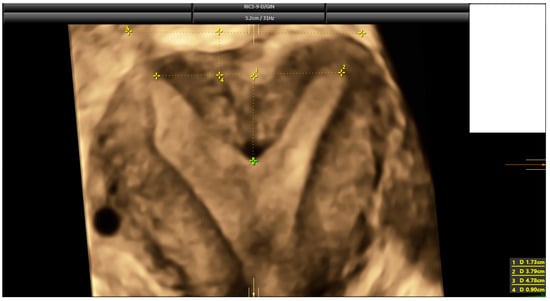

2.3. Ultrasound Evaluation

- Ludwin, A.; Martins, W.P. Correct measurements of uterine fundal internal indentation depth and angle: An important but overlooked issue for precise diagnosis of uterine anomalies. Ultrasound Obstet. Gynecol. 2021, 58, 497–499. [Google Scholar] [CrossRef] [PubMed]